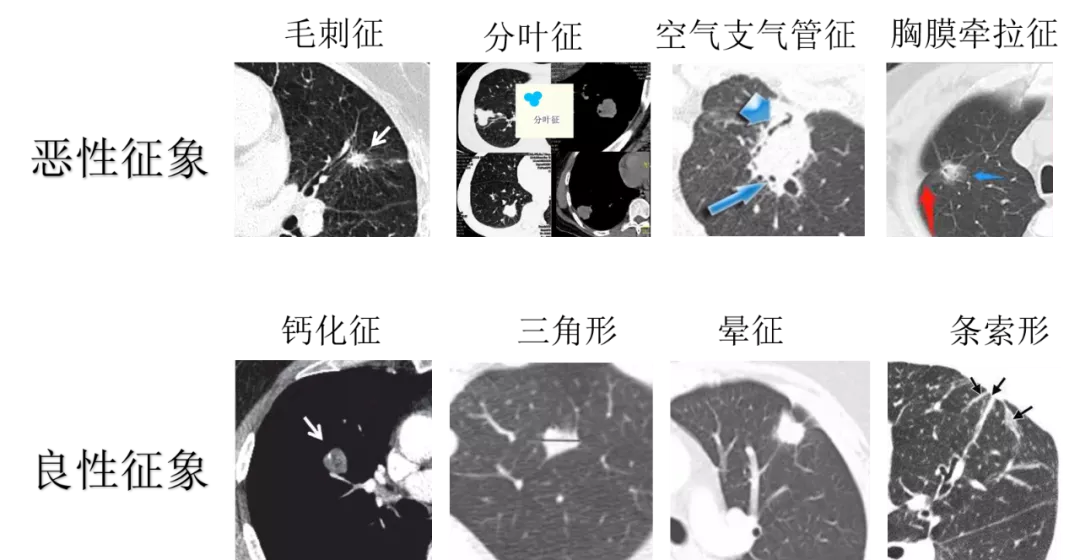

比如,

分葉徵——惡性腫瘤有異質性,細胞生長速度不完全一致,不會表現為一個完全的圓形或橢圓形,而是像三葉草一樣出現分葉。

空氣支氣管徵——由於腫瘤細胞生長牽拉,會導致支氣管被牽拉擴張,表現為空氣支氣管徵。

毛刺徵——腫瘤細胞向周圍延伸並引起免疫反應會形成毛刺,以短毛刺為主。

胸膜牽拉徵——腫瘤組織臨近胸膜時,細胞生長會牽拉周圍的胸膜,形成胸膜牽拉徵。

良性結節,與之相反,也有一些讓人一看就知道是良性的特徵。

鈣化——鈣化是良性結節一個比較明顯的特徵。

三角形——如果在CT不同層面發現結節是三角形,那大概率是淋巴結等良性結節。

條索形——如果在CT不同層面重建後發現肺結節表現為條索性,很可能是纖維增生。

暈徵——暈徵是指在肺結節周圍形成的光暈一樣的改變,這是炎性結節的一個特徵性表現。

過於專業,看不懂也不怪你們

就像警察不能看長相判斷好人壞人一樣,我們也不能完全靠這些特徵判斷,因為這些影像特徵並不絕對,良性病變也可以有毛刺,惡性結節也可以有暈徵,這些特徵只是增加了一些概率和可能性,還是需要醫生綜合判斷。